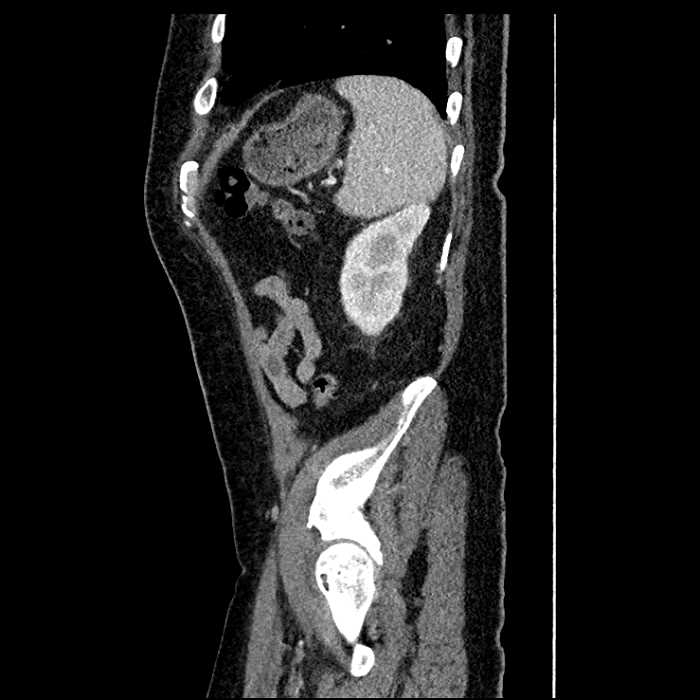

• Large fluid density structure in hepatic segments 7 and 8 measuring 10 x 7 x 7 cm with internal septation and circumferential ill-defined low density compatible with edema

• Peripherally enhancing subcapsular collections along the anterior margin of the left hepatic lobe measuring 3 x 1 cm and 2 x 1 cm

• Clearly marginated fluid density structure in segment 7 and several other scattered tiny hypodensities, which likely represent cysts

Acute sigmoid diverticulitis complicated by a small contained perforation and a large abscess in the right hepatic lobe. Additional small subcapsular abscesses along the anterior margin of the left hepatic lobe.

• The classic CT imaging appearance is a double target sign with internal low density surrounded by an internal enhancing rim (capsule) and a low density external rim (edema)

Hepatic abscess showing the double target sign with low density internally surrounded by a thin inner enhancing rim (red arrow) and ill-defined outer low density rim (yellow arrow). Blue arrow indicates an internal septation. Red arrows: additional smaller subcapsular abscesses. Red arrow: focal contained perforation associated with diverticulitis.